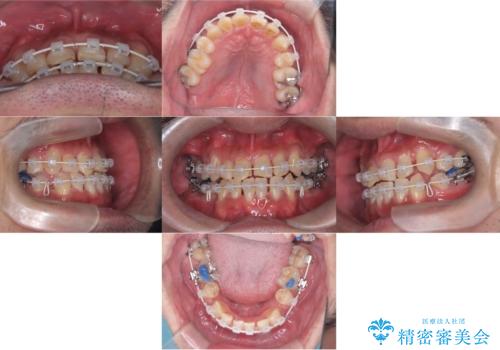

骨格性Ⅲ級を示しましたが、構成咬合位がとれたことから反対咬合と叢生改善のため、上下左右第一小臼歯を抜歯しワイヤー矯正を行いました。途中、バイトアップを行っています。

期間:3年3か月